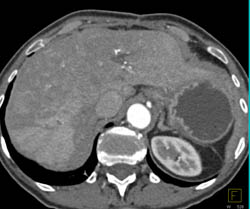

Focal Nodular Hyperplasia (FNH)